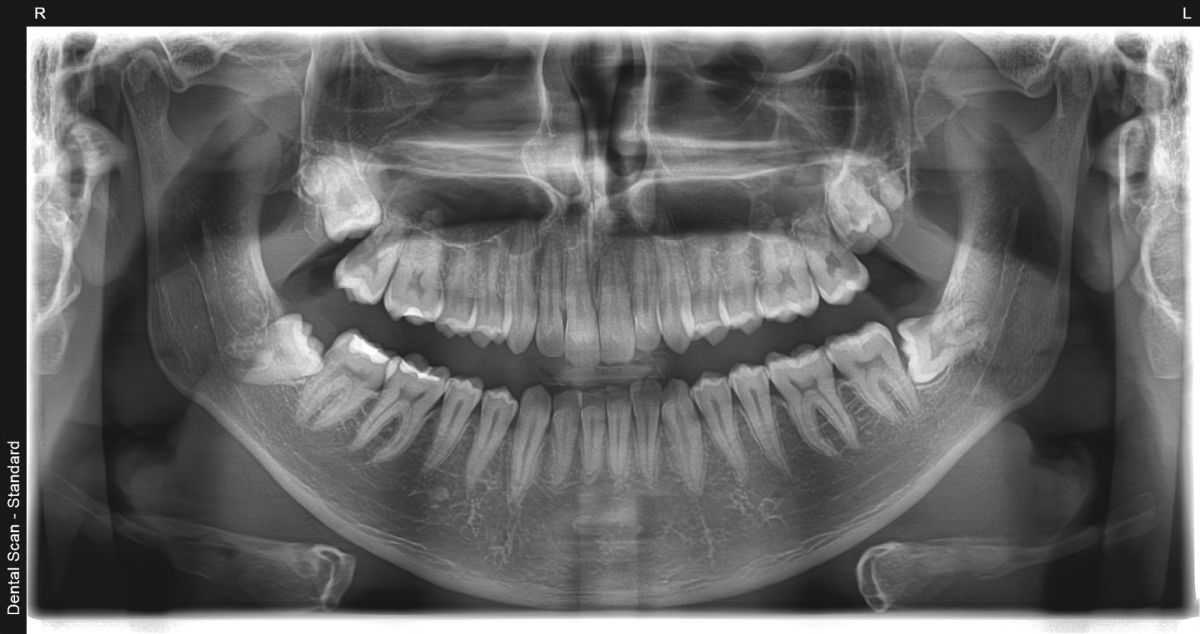

U svetu dentalne dijagnostike, ortopan (poznat i kao ortopantomogram) predstavlja zlatni standard. To je digitalni panoramski rendgenski snimak koji pruža sveobuhvatan, dvodimenzionalni prikaz celokupnog viličnog sistema. Za razliku od pojedinačnih snimaka zuba, koji se fokusiraju na izolovanu regiju, ortopan nam donosi „širu sliku“.

U Dental Scan centru, koristeći najsavremenije digitalne senzore, omogućavamo uvid u:

- Kompletan niz zuba u gornjoj i donjoj vilici;

- Stanje korenova i okolne koštane strukture;

- Temporomandibularne zglobove i njihovu funkcionalnost;

- Maksilarne sinuse i njihov odnos sa korenima gornjih zuba;

- Položaj impaktiranih zuba, uključujući i problematične umnjake;

- Rano otkrivanje patoloških promena, kao što su ciste, granulomi ili tumori kosti.

- Ortopan (ortopantomografija) – panoramska 2D radiografska tehnika koja u jednom snimku prikazuje obe vilice, sve zube i korenove, vilične zglobove i okolne koštane strukture.